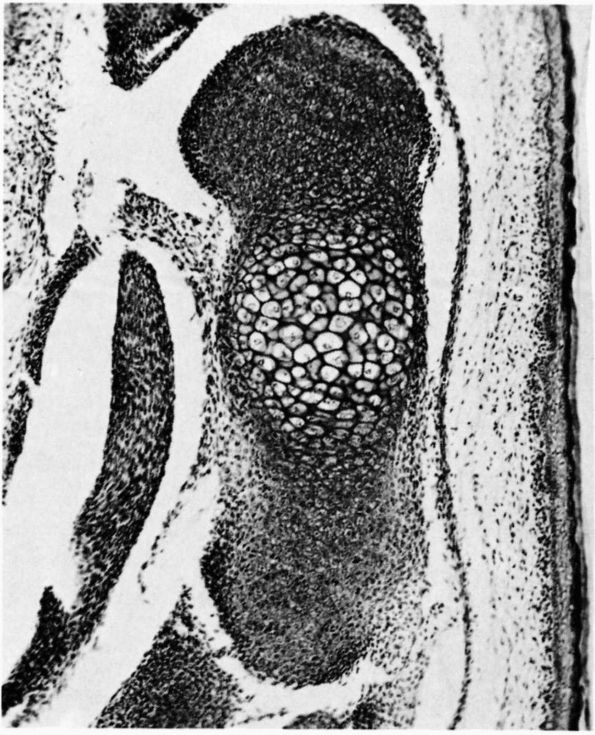

the calcified cartilage zone (Figure 1-18 and Color Figure 1-1).

makes it possible for them to produce precisely directed longitudinal

bone growth. The growth cartilages increase their volume and therefore

bone length by synthesizing new matrices and by cell swelling. The

organization of the growth cartilage matrix and the surrounding fibrous

tissue directs the increasing volume of cells and matrices, so that it

produces longitudinal bone growth. In the region of the growth

cartilage nearest to the metaphysis, the longitudinal cartilage septae